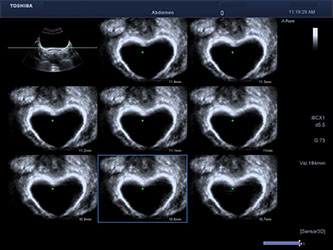

Ultraschall

- Schwangerschaft, inklusive Farbdoppler und 3D Babyfernsehen